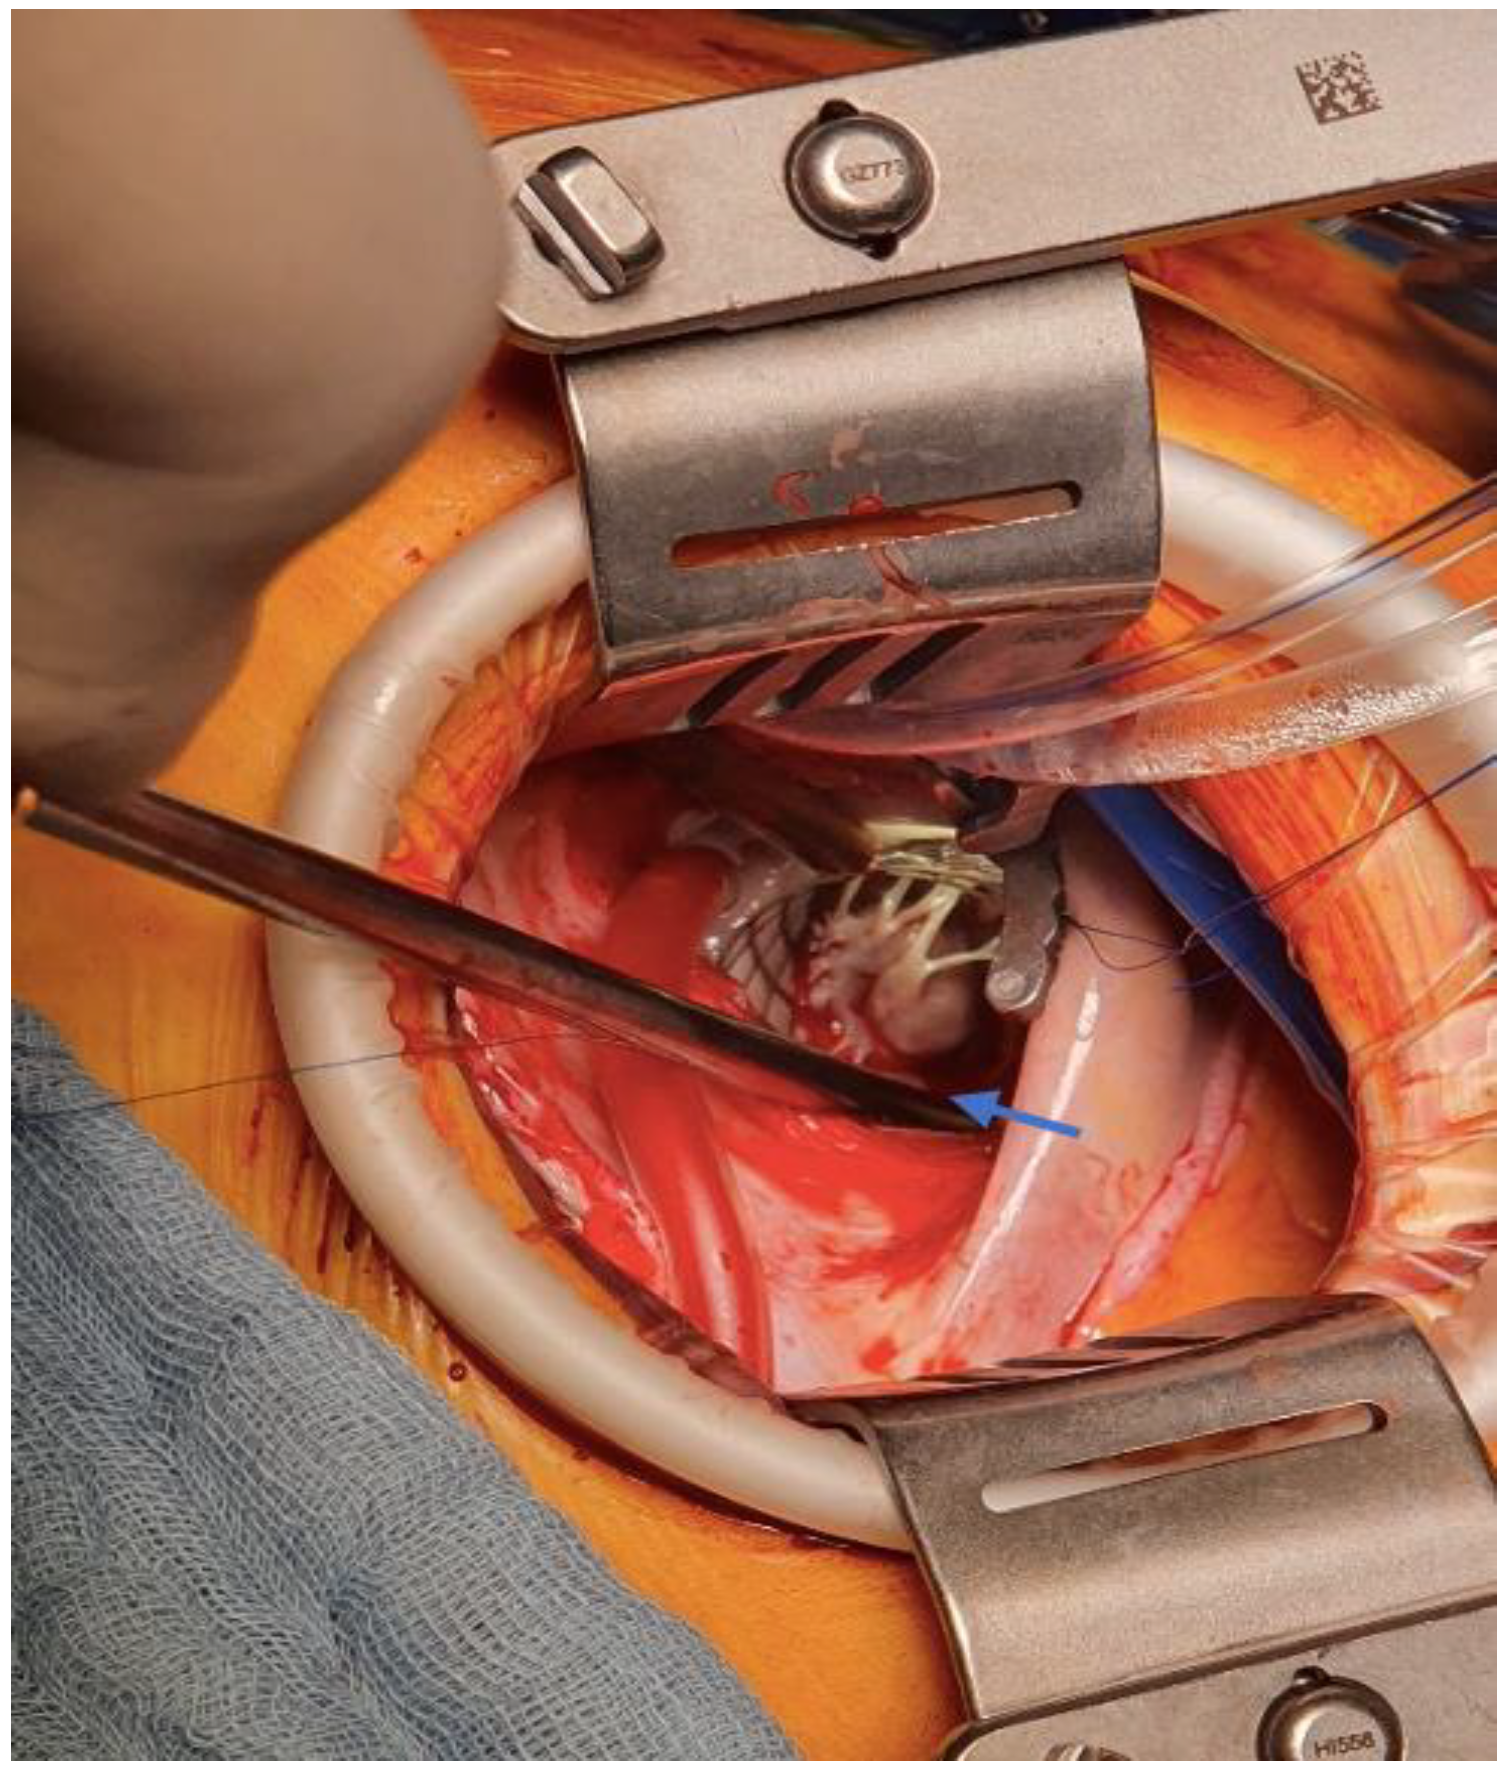

2. Case Report